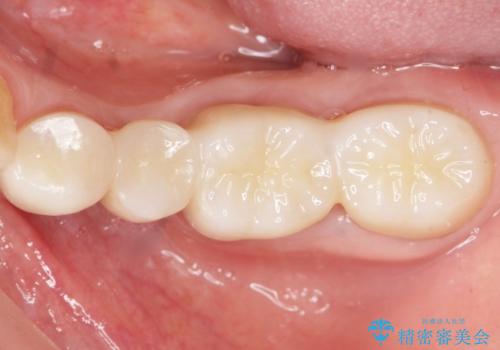

ご希望通り歯を抜かずに残すことができ、喜んで頂けました。

セルフメンテナンスしやすいよう、ブリッジと歯ぐきの間に歯間ブラシを通すことができるように作製しています。

咬合関係により奥歯の負担が大きいため、今後も注意深く経過観察していく予定です。

治療結果にご満足頂けたため上顎前歯の治療もご希望され、現在治療中です。

被せ物の種類:オールセラミッククラウン ベレッツァ